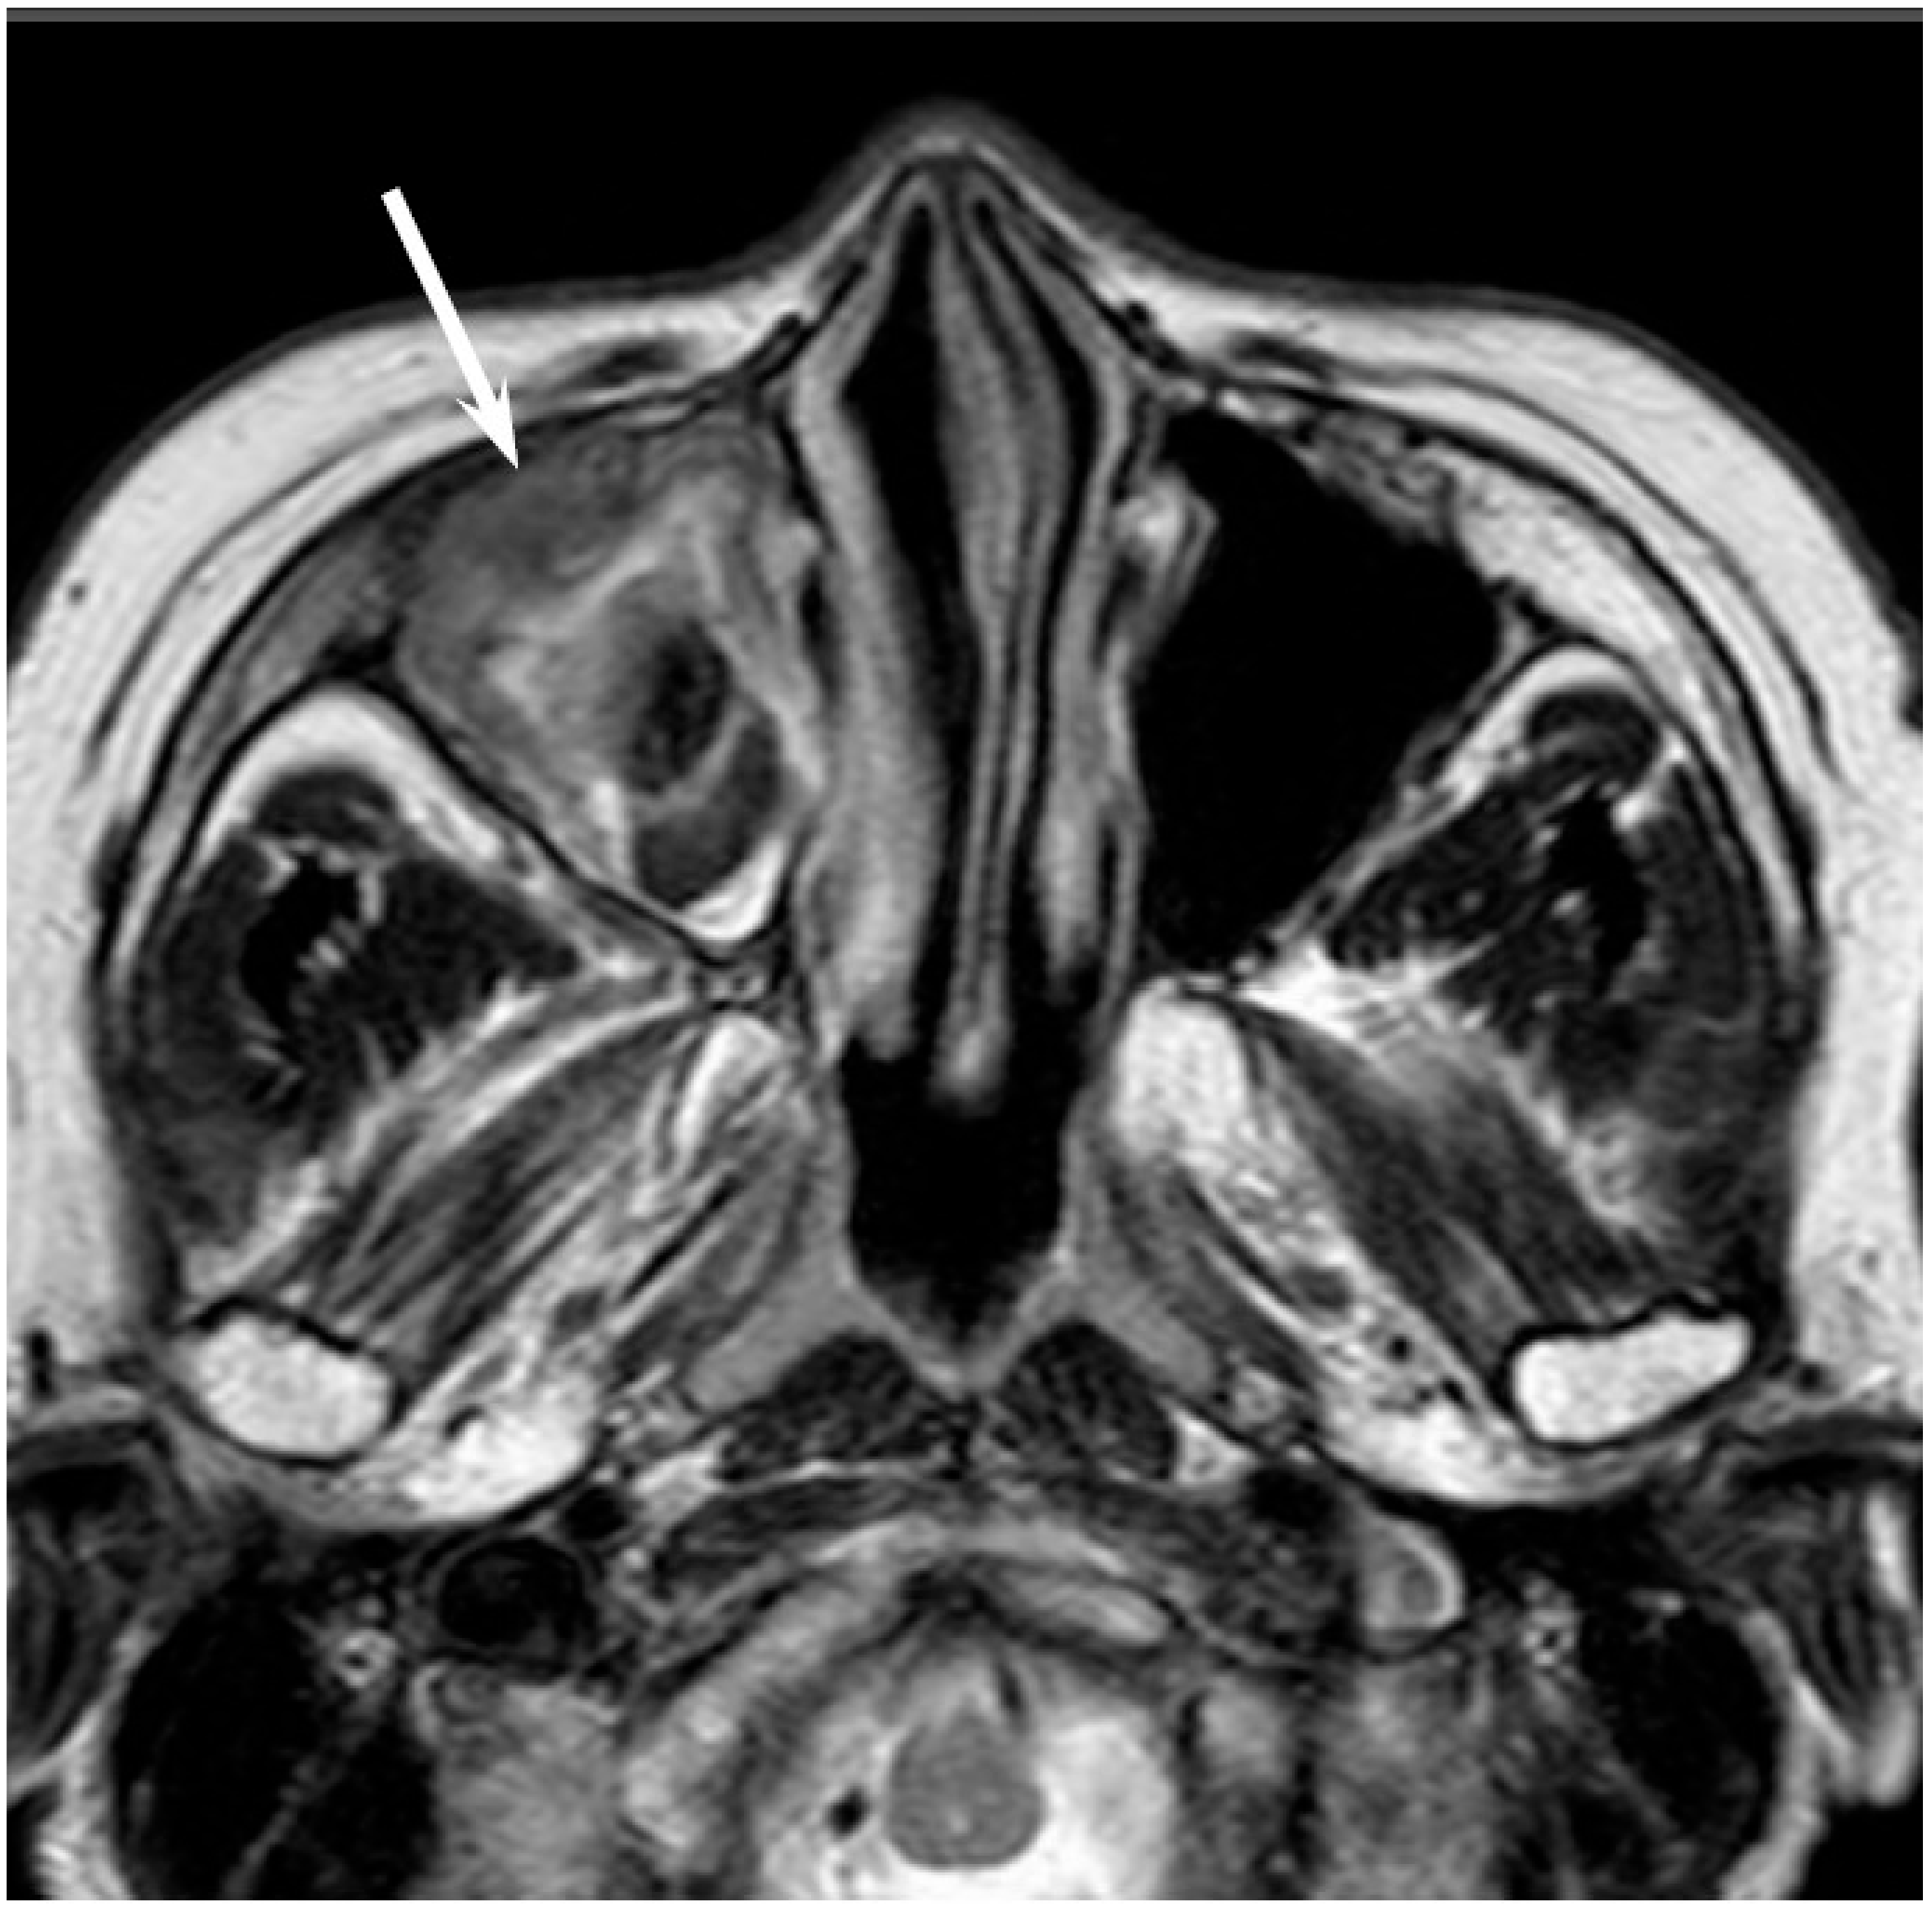

Figure 3. Adenoid cystic carcinoma of the left maxillary sinus and nasal cavity. T2-weighted image showing a well-demarcated, lobulated, heterogeneously and strongly hyperintense lesion (arrow).

Low-grade sinonasal ACCs may present as polypoid lesions that remodel the bone and mimic a simple polyp, whereas high-grade sinonasal ACCs may present as large irregular masses with bone destruction and heterogeneous density or signal intensity [18]. The growth pattern of maxillary sinus ACCs can be classified into expansile type with minimal bony defects and destructive type with extensive bony defects, and these tumors usually extend to the nasal cavity and, occasionally, to the retroantral fat pad, pterygopalatine fossa, or orbit [19]. ACCs show isointensity on T1WI and iso- to hyperintensity on T2WI, depending on the amount of cellularity (Figure 3). ACCs exhibit the greatest propensity for perineural spread, and the maxillary division of the trigeminal nerve is most commonly affected by sinonasal ACCs. These tumors sometimes easily extend into intracranial components including the cavernous sinus and the Gasserian ganglion, which are far away from the original site [20,21]. Furthermore, for the surgeons, it is often important to first evaluate on images whether the tumor is resectable or not and far away from vital structures. In cases with an advanced tumor, fluid collection and thickened mucosa caused by the isolated sinuses sometimes make it difficult to diagnose and stage the disease.